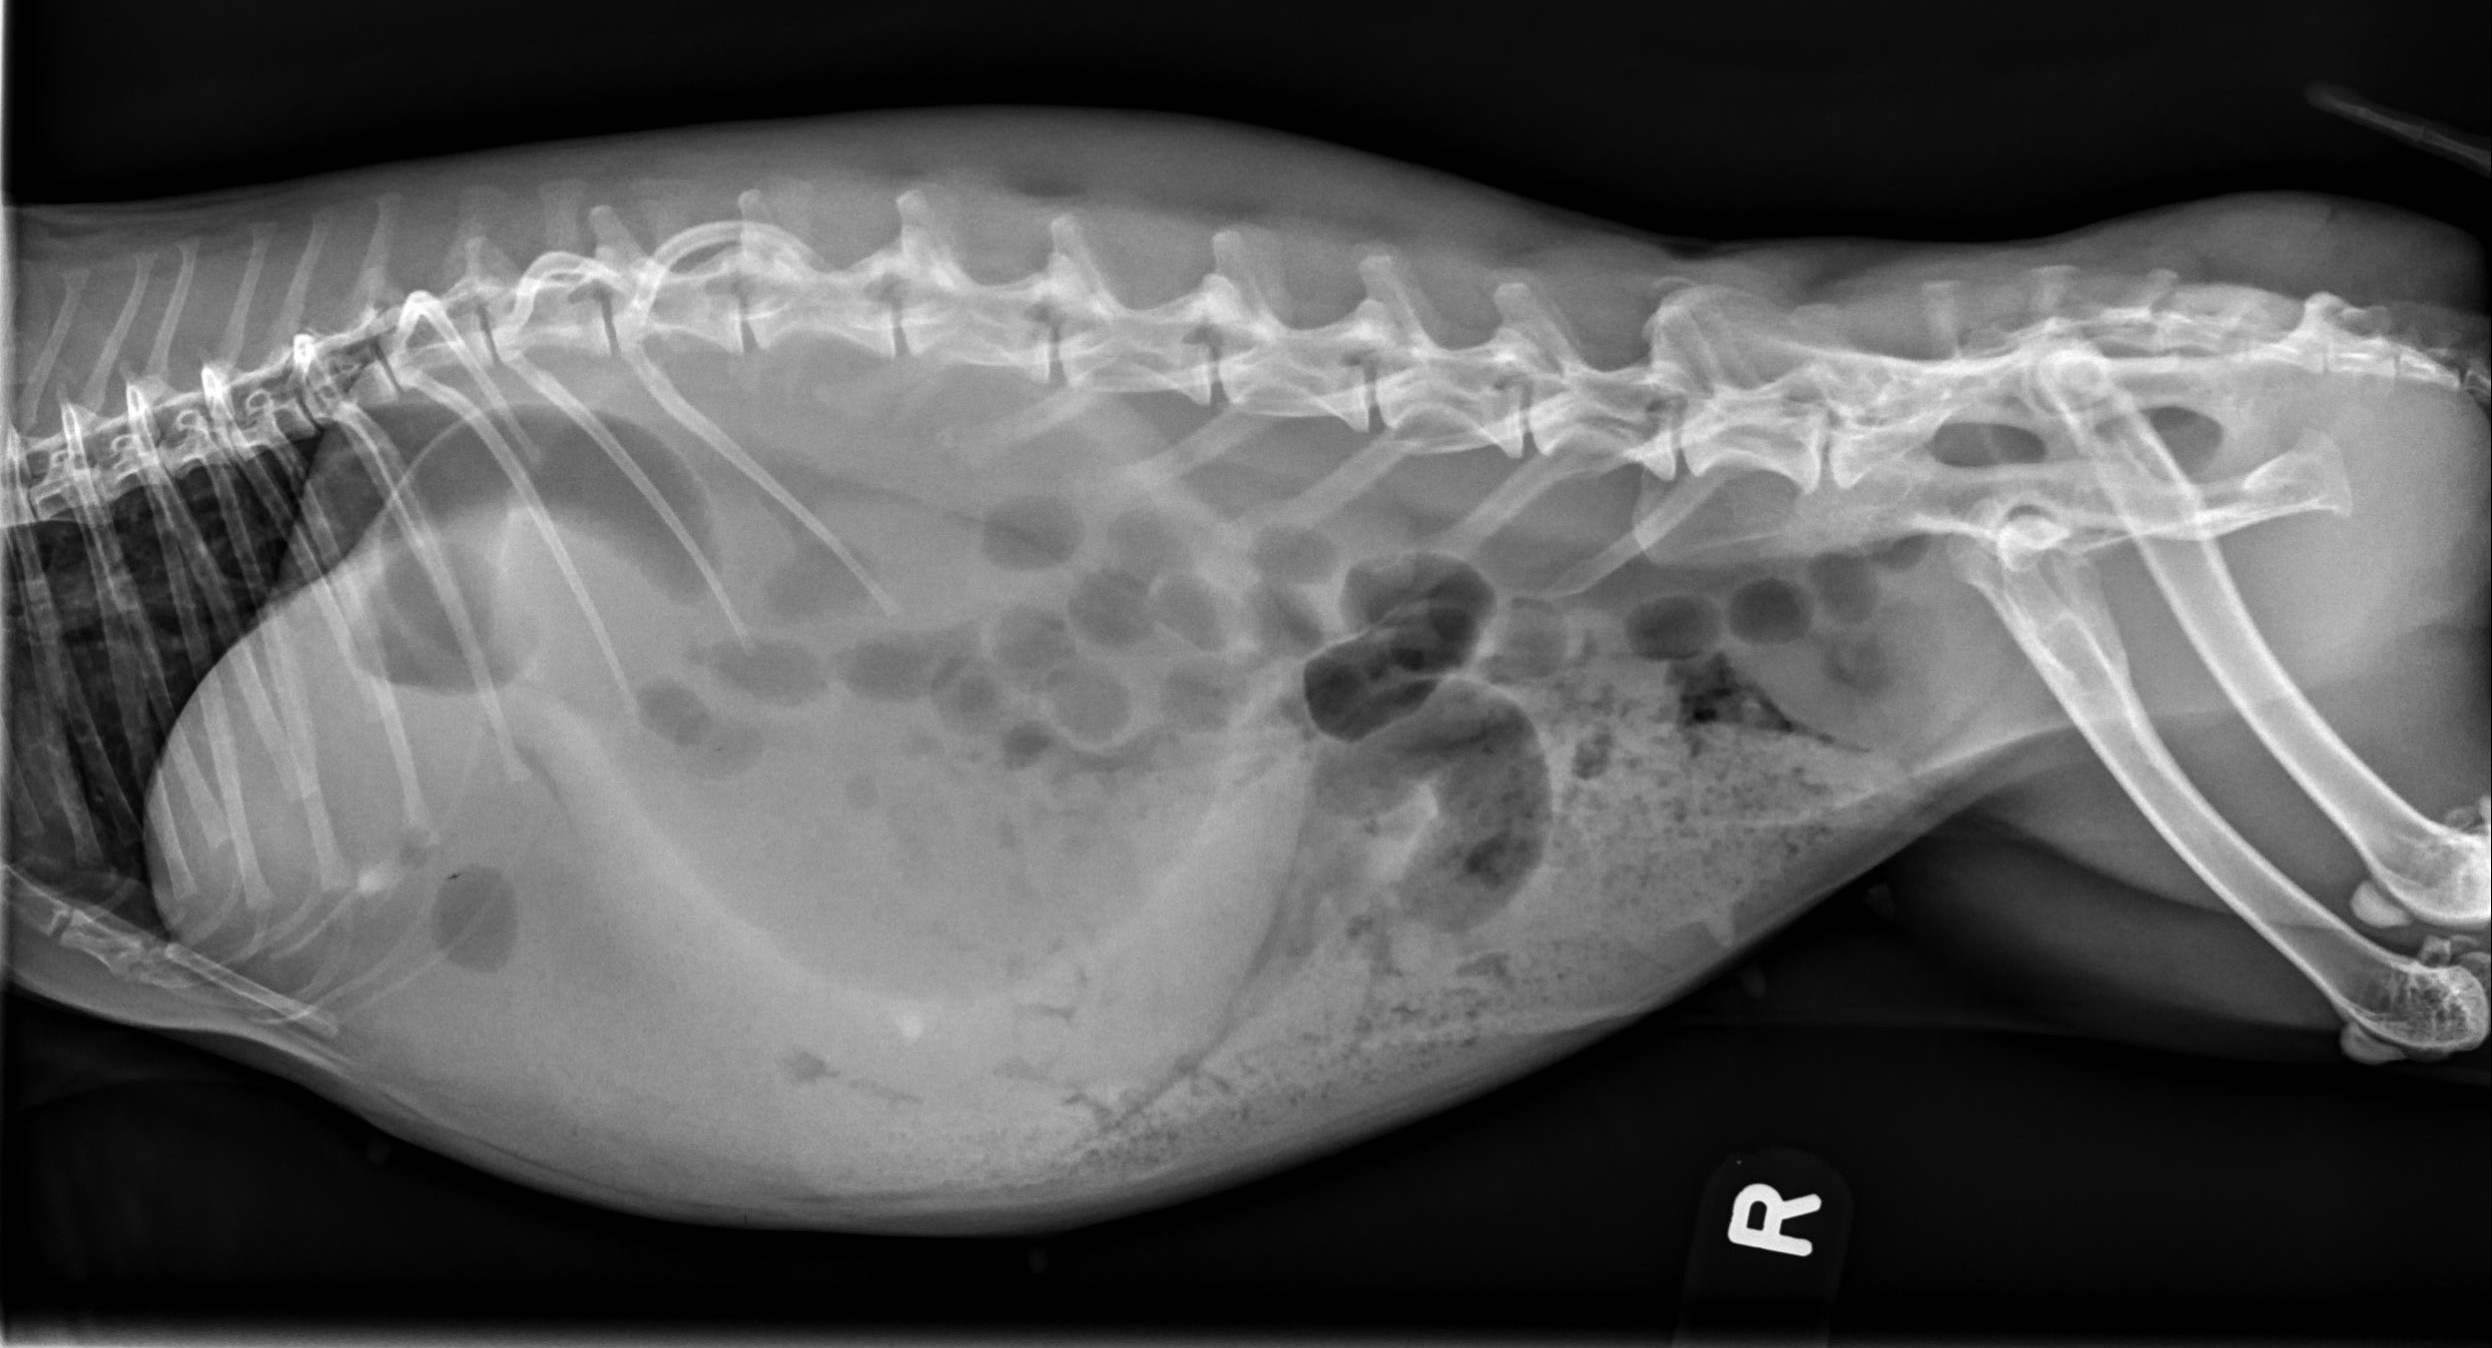

Radiographic Patterns: Ileus vs. Gastric Outflow Obstruction

Radiographs can help differentiate between RGIS and a potentially more serious gastric outflow obstruction (although to be honest, I approach treatment the same way for both in the first 24 hours).

RGIS radiographic signs:

• Dehydrated, radiodense stomach contents

• Circumferential line of gas around dehydrated contents

• +/- cecal distension

Gastric outflow obstruction:

• Enlarged, fluid-filled stomach

• Dorsal gas cap

• Stomach extends beyond last rib

• 2 populations of small intestine often present